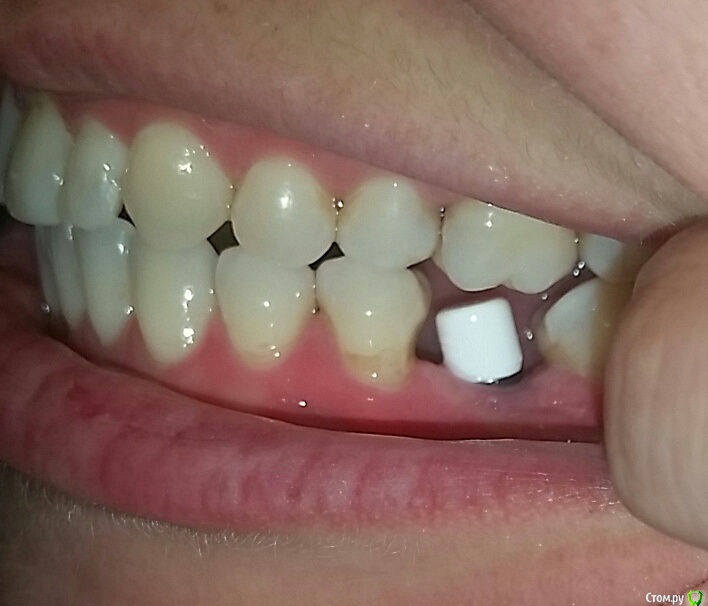

Natalia105 Опубликовано 6 апреля, 2017 Поделиться Опубликовано 6 апреля, 2017 Здравствуйте уважаемые врачи. У меня установлены три импланта в июне 2016 года - на зубы 19, 30 и 31, прижились хорошо. При попытке установки коронок выяснилось, что коронки слишком маленького размера (импланты 30 и 31 стоят слишком близко друг к другу и нет достаточно места чтобы сделать коронки крупнее). Между десной и коронками в глаза бросается металл. Выглядит все это ужасно некрасиво и неестественно. Доктор уверяет меня, что красота в молярах это не главное, а главное это функциональность. Но разве одно с другим несовместимо? Тем более за такие деньги... Да и маленькие коронки тоже ведь снижают функциональность. Коронки сделали только в марте, потому что ждали снятия брекетов. Я пока отказалась от установки таких коронок до выяснения следующих вопросов: 1. Размеры коронок 30 и 31 зубов слишком маленькие, так как недостаточно места. Импланты стоят слишком близко друг к другу, что это - ошибка доктора? Он делал операцию "на глазок" без шаблона (возможно потому, что у меня в тот момент были брекеты). На мои претензии доктор ответил, что кость в том месте мягкая и он не мог поставить 31 имплант дальше. Хотя другой доктор до этого говорил, что с костью у меня там все в порядке (я делала 3D рентген)... Но ведь если кость там действительно мягкая - доктор должен был нарастить ее, не так ли? Потом поставить туда широкий имплант + индивидуальный абатмент, и в итоге коронку нормального размера (это ведь моляр). Так ведь, или я ошибаюсь? 2. В моей ситуации (если не удалять импланты) можно и нужно ли сделать на 31 зуб широкий индивидуальный абатмент и более длинную коронку? При этом с нормальной нагрузкой на имплант (чтобы не расшатался) и чтобы коронка не сломалась под нагрузкой? Или как вариант - одну большую длинную коронку на два импланта? 3. На рентгене видно, что импланты 30 и 31 недостаточно покрыты костью - нужно ли нарастить кость? Или и так сойдет? Если оставить так - не будет ли рецессия кости и не приведет ли в скором времени к потере импланта? 4. Между десной и коронками в глаза бросается металл. Доктор уверял меня, что наращивать десну мне не нужно, потому что там будут скапливаться бактерии (между коронкой и десной), что приведет к воспалению десны и другим неприятным последствиям. Так ли это? Но ведь если десну не нарастить, то на торчащий абатмент будет наматываться еда (особенно мясо) - что тоже неприятно и возможно больно. Да и выглядит неэстэтично... Что же мне делать - наращивать десну или нет? 5. Если оставить 30 и 31 коронки такими маленькими, то имеет ли смысл тогда сделать еще один имплант на 32-й зуб? Во-первых, чтобы продлить зубной ряд - жевательная способность улучшится, во-вторых, нагрузка на 30 и 31 уменьшится (меньше вероятности, что коронка 31-го зуба сломается или расшатается сам имплант 31-го зуба). Ссылка на комментарий

Bier Опубликовано 10 апреля, 2017 Поделиться Опубликовано 10 апреля, 2017 у вас виден край абатмента на котором сидит коронка. По снимкам не очень ясно, можно ли еще спилить 1мм на абатменте, чтобы коронка доходила до десны (разумеется коронку нужно будет новую делать) Ссылка на комментарий